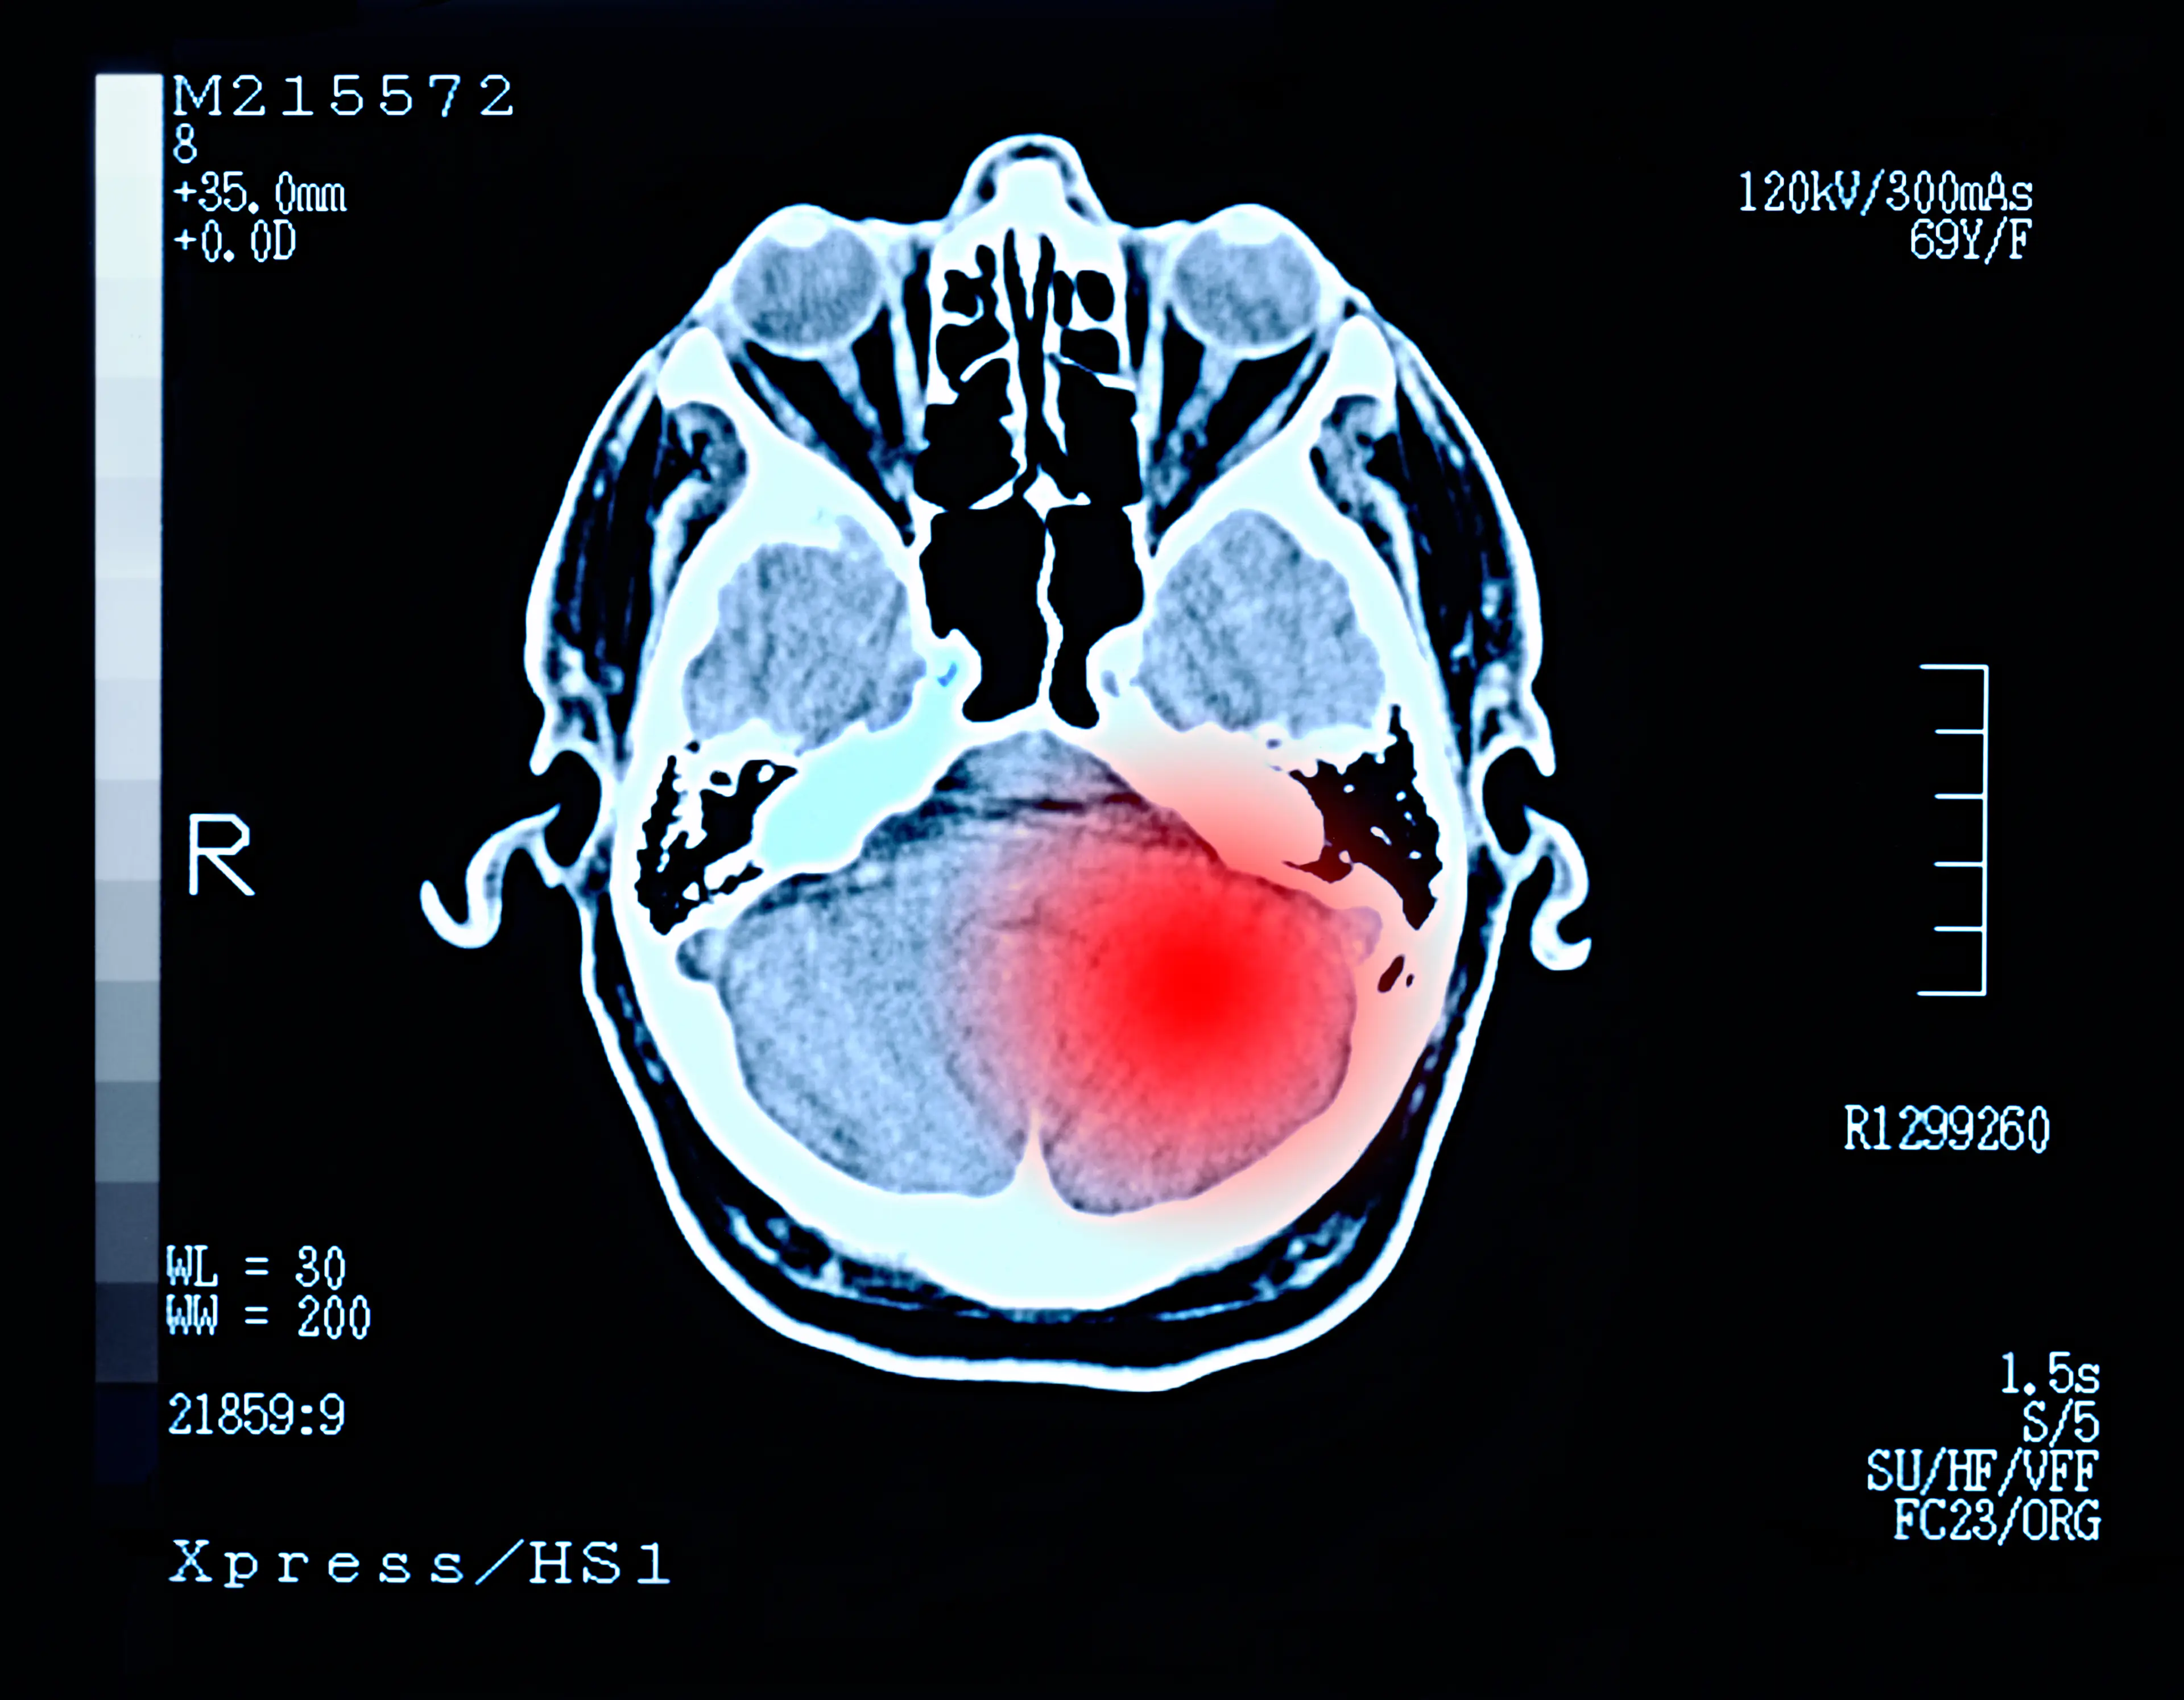

Experts have revealed that a very specific change in personality may be an early sign of rare brain cancer known as glioblastoma, which is a type of glioma.

Glioblastoma (GBM) is known as one of the most common, complex, treatment-resistant, and deadliest cancers that completely devastates the brain, which, as we know, controls cognition, mood, behaviour, and personality, as well as every function of each organ and body part.

What are the symptoms of glioblastoma?

Now, according to Aaron Cohen-Gadol, MD, some of the most common symptoms of gliomas include personality changes and irritability.

Other symptoms include:

- Recurring headaches

- Drowsiness

- Unprovoked nausea and vomiting

- New-onset seizures

- Difficulty speaking

- Loss of balance

- Personality changes and irritability